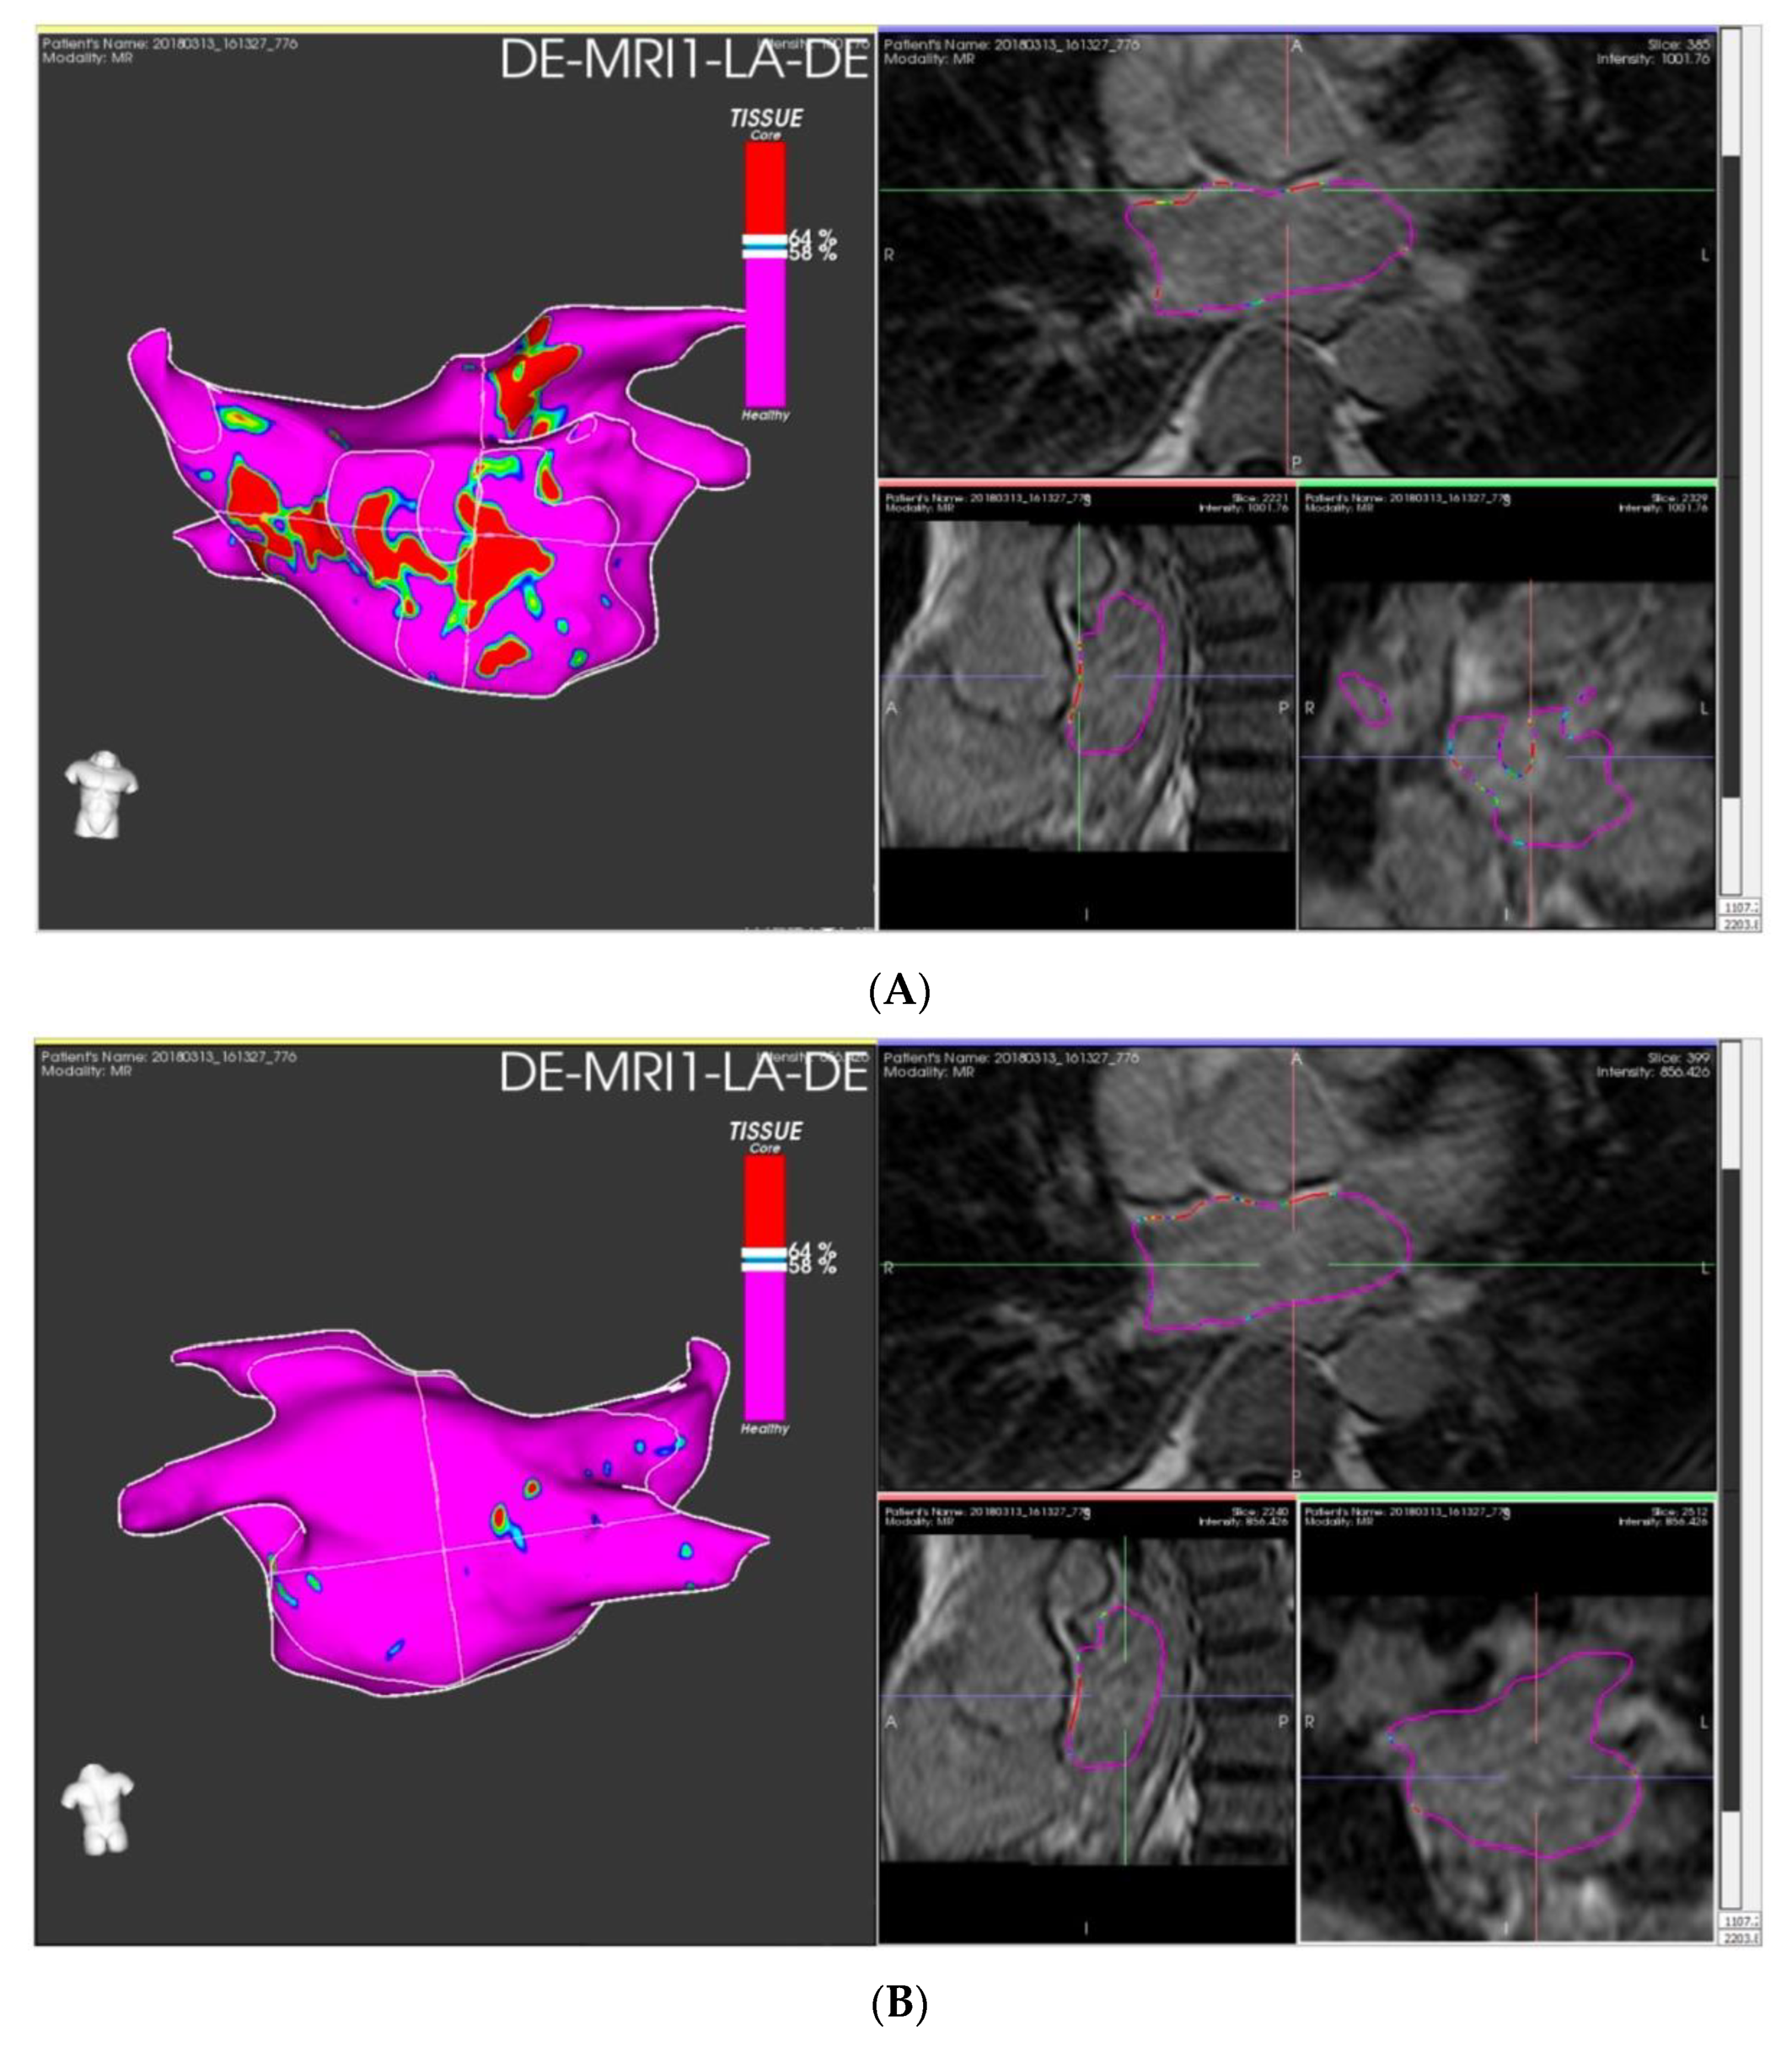

4.2. Procedure Induced Ablation Scars

- Chelu, M.G.; King, J.B.; Kholmovski, E.G.; Ma, J.; Gal, P.; Marashly, Q.; Aljuaid, M.A.; Kaur, G.; Silver, M.A.; Johnson, K.A.; et al. Atrial Fibrosis by Late Gadolinium Enhancement Magnetic Resonance Imaging and Catheter Ablation of Atrial Fibrillation: 5-Year Follow-up Data. J. Am. Heart Assoc. 2018, 7, e006313. [Google Scholar] [CrossRef]

- Marrouche, N.F.; Wilber, D.; Hindricks, G.; Jais, P.; Akoum, N.; Marchlinski, F.; Kholmovski, E.; Burgon, N.; Hu, N.; Mont, L.; et al. Association of Atrial Tissue Fibrosis Identified by Delayed Enhancement MRI and Atrial Fibrillation Catheter Ablation: The DECAAF Study. JAMA J. Am. Med. Assoc. 2014, 311, 498–506. [Google Scholar] [CrossRef]

- McGann, C.; Akoum, N.; Patel, A.; Kholmovski, E.; Revelo, P.; Damal, K.; Wilson, B.; Cates, J.; Harrison, A.; Ranjan, R.; et al. Atrial Fibrillation Ablation Outcome Is Predicted by Left Atrial Remodeling on MRI. Circ. Arrhythm Electrophysiol. 2014, 7, 23–30. [Google Scholar] [CrossRef]

- Marrouche, N.F.; Wazni, O.; McGann, C.; Greene, T.; Dean, J.M.; Dagher, L.; Kholmovski, E.; Mansour, M.; Marchlinski, F.; Wilber, D.; et al. Effect of MRI-Guided Fibrosis Ablation vs. Conventional Catheter Ablation on Atrial Arrhythmia Recurrence in Patients With Persistent Atrial Fibrillation: The DECAAF II Randomized Clinical Trial. JAMA 2022, 327, 2296–2305. [Google Scholar] [CrossRef] [PubMed]

- Fochler, F.; Yamaguchi, T.; Kheirkahan, M.; Kholmovski, E.G.; Morris, A.K.; Marrouche, N.F. Late Gadolinium Enhancement Magnetic Resonance Imaging Guided Treatment of Post-Atrial Fibrillation Ablation Recurrent Arrhythmia. Circ. Arrhythm Electrophysiol. 2019, 12, e007174. [Google Scholar] [CrossRef]